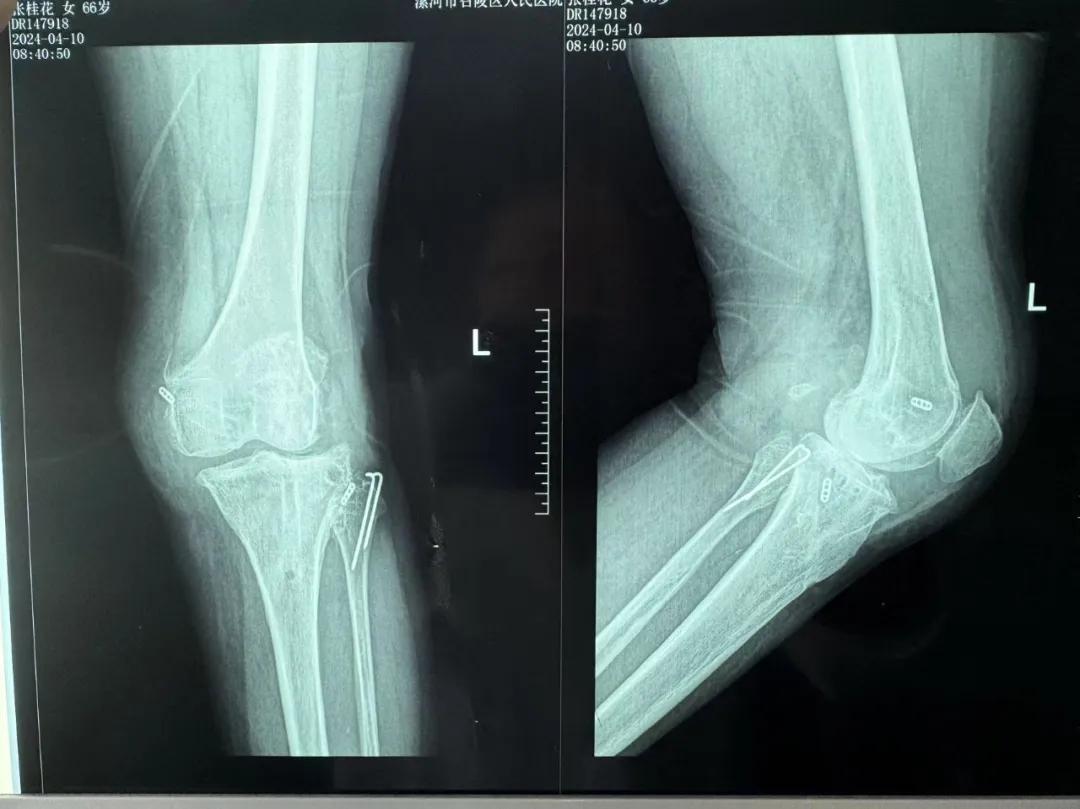

患者來院后,漯河市骨科醫(yī)院(漯河醫(yī)專二附院、漯河市立醫(yī)院)主治醫(yī)師康樂便成了她的管床醫(yī)生。在經(jīng)過詳細的術前診斷與檢查后,關節(jié)外科主任李付彬組織科室團隊針對患者的診斷情況進行術前討論——患者為重度膝關節(jié)骨關節(jié)炎,需進行人工關節(jié)置換。但術前的評估結果顯示:患者膝關節(jié)側(cè)方不穩(wěn)定,單純行初次表面膝關節(jié)置換,術后仍會存在側(cè)方不穩(wěn)的情況,會影響術后效果以及假體使用年限,不僅無法完全恢復膝關節(jié)功能,還會加重患者的經(jīng)濟負擔。

為了盡可能給患者帶來更好的治療效果,減輕其經(jīng)濟負擔,經(jīng)綜合評估后,李付彬主任帶領團隊制定了最終的手術方案——決定使用髁限制性膝關節(jié)假體(LCCK)置換膝關節(jié)。作為解決患者病痛的最優(yōu)方案,這項手術具體實施的難度并不小,需要在術中根據(jù)截骨情況進行多次評估和實時調(diào)整,這就要求主刀醫(yī)生不僅要具備過硬的專業(yè)技術與能力,還要能夠結合自身的經(jīng)驗準確判斷、精準操作。

手術過程中,關節(jié)外科團隊為患者進行了標準截骨,經(jīng)過評估,患者膝關節(jié)仍存在膝關節(jié)側(cè)方不穩(wěn)定,便按照原定手術計劃使用LCCK假體進行了膝關節(jié)置換。經(jīng)過再次評估,患者膝關節(jié)穩(wěn)定性恢復,下肢力線正常,這臺高難度的LCCK膝關節(jié)置換手術在一小時內(nèi)便順利完成!術后第二天,患者就能夠自主下床負重活動,功能恢復良好。